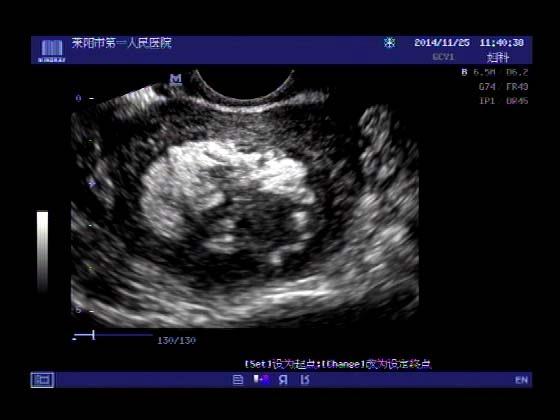

超声入门贴379---------粘膜下肌瘤(阴超的魅力)

女,43岁,月经量多3个多月,加重一个月

外院彩超检查提示:子宫后肌壁略高回声团------肌瘤?息肉?,盆腔少量积液

今天来我院检查:

巧妇难为无米之炊,经腹部超声确实很难定,阴超一目了然,乡镇医院诊断水平的提高更迫切的需要高档仪器的引进!